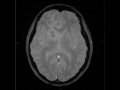

Brain Abscesses, Multiple

13-year-old male with a gradually obtunded mental status and fevers of up to 105 degrees Fahrenheit. Numerous round lesions are demonstrated within the supratentorial compartment with T1-hypointense and FLAIR-hypointense central signal intensity. The lesions have a thin margin of T1-isointense signal, and are surrounded by vasogenic edema. There is prominent diffusion restriction within the central portions of the lesions with faint linear regions of signal loss in the walls of the lesions on the susceptibility weighted images. The post contrast images demonstrate peripheral enhancement. The findings are compatible with multiple brain abscesses. There are four distinct stages in the development or evolution of a brain abscess consisting of early cerebritis, late cerebritis, early capsule and late capsule formation. After biopsy, this patient grew a Streptococcus sp., but a primary site of infection was never determined. Had the patient not presented in a septic state, the differential would have included: metastatic disease, subacute infarction, demyelinating disease and radiation necrosis.